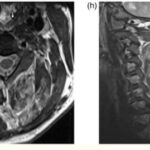

En esta investigación que se viene señalando, se puede mencionar el caso de un joven de 16 años, con alteración aguda del estado mental por inhalación de vapor de heroína. Se le efectuó una RM que evidenció hiperintensidades en T2 de la sustancia blanca simétrica difusa infratentorial y supratentorial. El diagnóstico clínico en este caso fue rabdomiólisis, que afecta predominantemente la musculatura posterior del cuello(21) (ver Imágenes 11 y 12).

Otro caso que merece ser comentado es el de un adolescente de 15 años que presentó encefalopatía y signos extrapiramidales por ingestión de metadona. La RM evidenció focos de infartos agudos en el caudado y putamen, así como infartos corticales de la línea divisoria de aguas parietales(21) (ver Imagen 13).